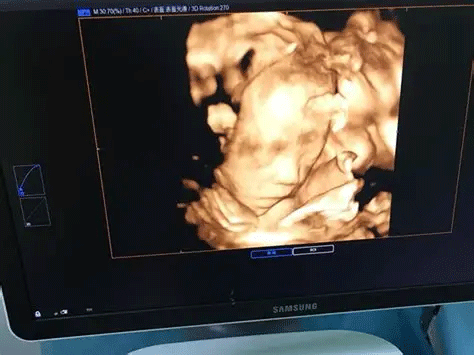

三维彩超,即彩色多普勒超声检查的一种,检查图像呈土黄色,通过多普勒超声仪器发出超声波,对体内各项器官进行成像。三维即其图像是立体的,可以更直观的看到器官的形态,及时发现病变并进行治疗。三维彩超常用于产检,用来判断胎儿的生长发育的情况或是否出现畸形等。

产检中,三维彩超通过测量子宫纵径、子宫体横径、子宫前后径这三条径线来观察胎儿是否正常。以及通过三维立体的成像,可以清晰的显示出胎儿各个内脏器官,以及面部器官、四肢的情况,来简单的判断胎儿是否存在畸形,包括胎儿是否患有先天性心脏病也是能够检查出来的。

24周的胎儿,其身体结构的生长发育已经很完善了,且胎儿大小也很合适,这时候做三维彩超可以很直观的看到胎儿的五官四肢、以及内脏器官,还能了解胎儿双顶径、头围、腹围、股骨长等发育情况。

目前临床上三维彩超检查是直接对胎宝宝先天头面部畸形的判断,可以拍到宝宝生长发育的局部立体图像。而四维相对于三维来说,会更清晰,对胎宝宝畸形,如唇腭裂、四肢发育畸形、脑膜膨出、脊柱裂、腹壁裂和心血管畸形等能够做早期诊断,并且能够立体显示胎宝宝的颜色、各器官的发育情况,甚至在母体内吸吮、睡觉等动态也可以捕捉到。。

三维和四维并不是彩色图片,只是和黑白色有差异,二者呈现的都是土黄色的画面。但三维的成像是静态的,是一张图片,而四维彩超则是动态的,像一张动图一样,并且有的医院会允许刻成光盘带回家收藏起来。